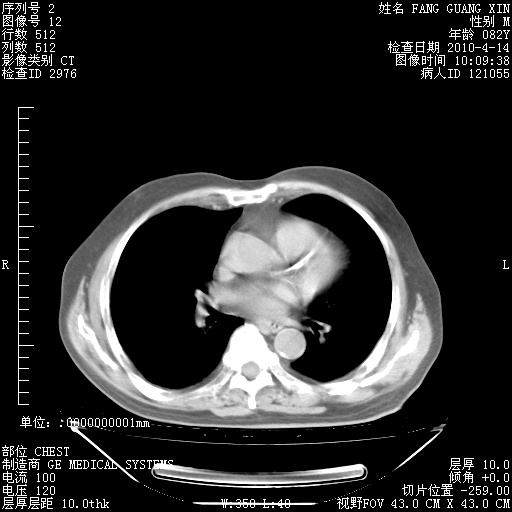

楼主| 发表于 2010-4-28 16:59 | 显示全部楼层

4月28日肺部CT——再次出现类似去年5月9日——透光度降低,(影像科认为)“间质性”改变。

4月28日肺部CT——再次出现类似去年5月9日——透光度降低,“间质性”改变。